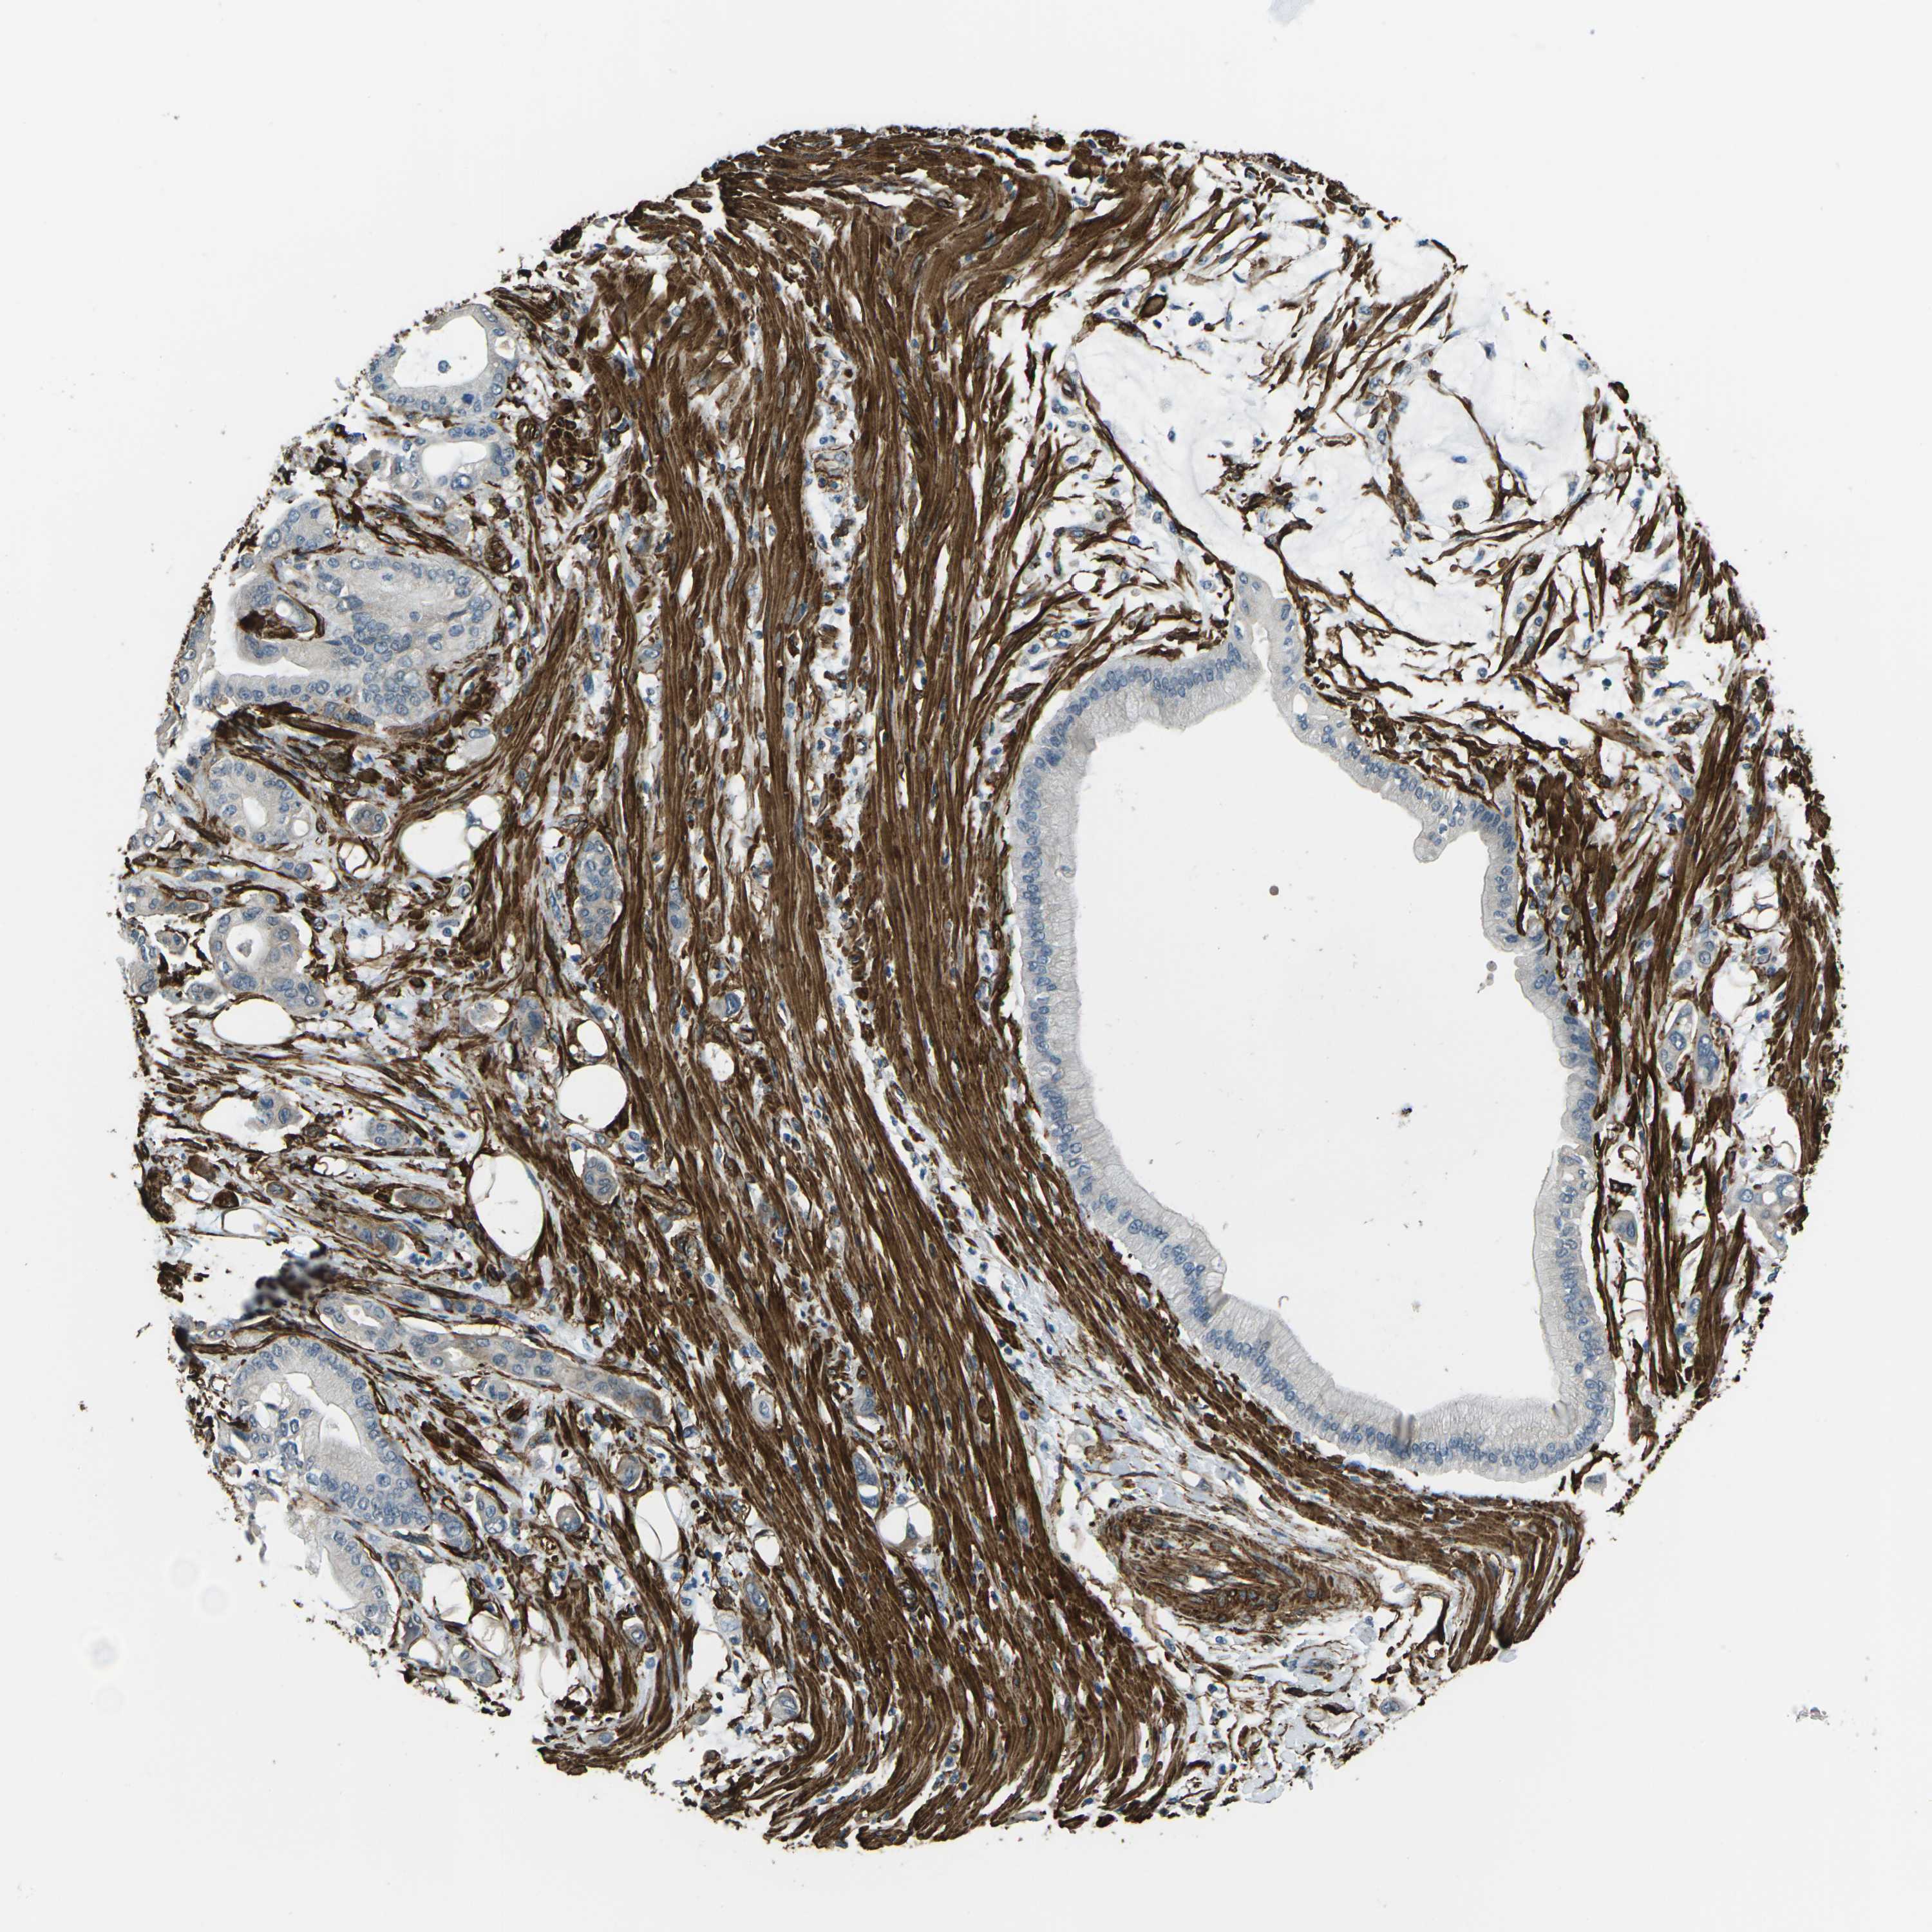

PANCREATIC CANCER - Protein expressioni

A mouse-over function shows sample information and annotation data. Click on an image to view it in a full screen mode. Samples can be filtered based on level of antibody staining by selecting one or several of the following categories: high, medium, low and not detected. The assay and annotation is described here.

Note that samples used for immunohistochemistry by the Human Protein Atlas do not correspond to samples in the TCGA dataset.

Antibody stainingi

Antibody staining in the annotated cell types in the current human tissue is reported as not detected, low, medium, or high, based on conventional immunohistochemistry profiling in selected tissues. This score is based on the combination of the staining intensity and fraction of stained cells.

Each image is clickable and will lead to virtual microscopy that enables deeper exploration of all samples and also displays staining intensity scores, fraction scores and subcellular localization as well as patient and tissue information for each sample.

Antibody HPA012316

Staining

High

Medium

Low

Not detected

Intensity

Strong

Moderate

Weak

Negative

Quantity

>75%

75%-25%

<25%

None

Location

Nuclear

Cytoplasmic/membranous

Cytoplasmic/membranous,nuclear

Adenocarcinoma, NOS

Adenocarcinoma, metastatic, NOS